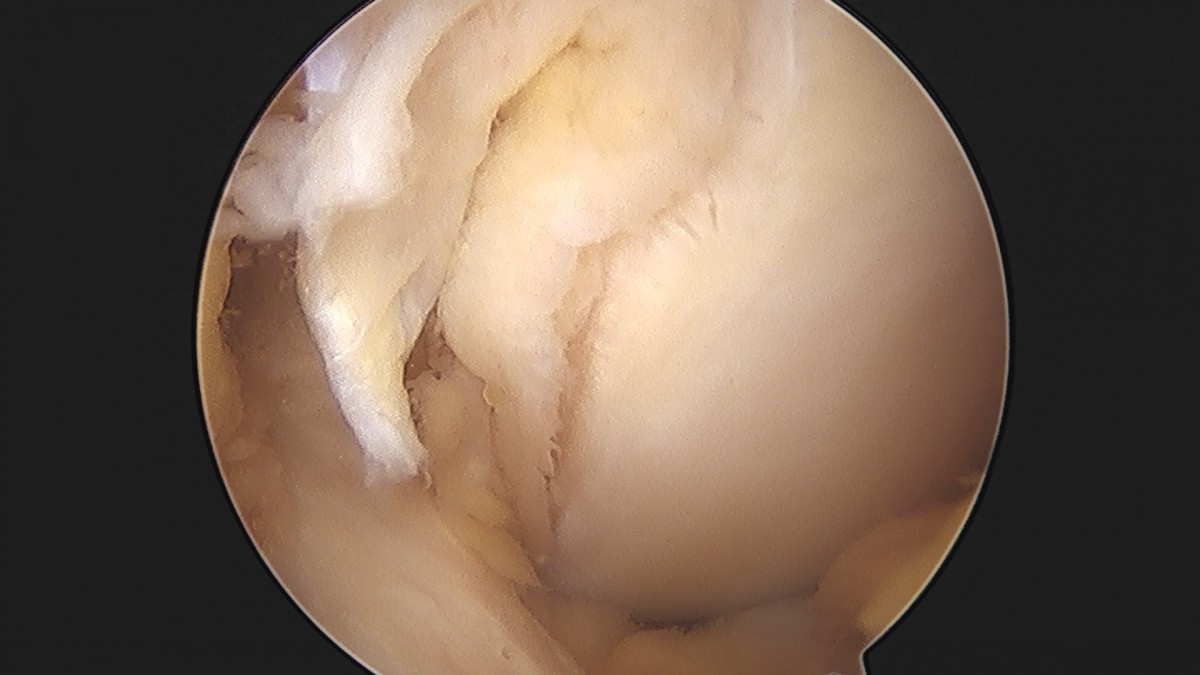

이재상원장님 무릎 반월상 연골판 절제술 김민O 환자

작성자 최고관리자 댓글 0건 조회 365회 작성일 25-09-16 16:10